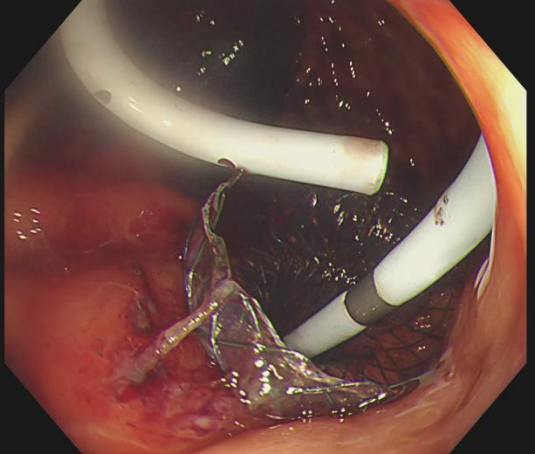

为确保引流充分持久,孙家琛创新性地在LAMS支架内,再叠加置入一枚“双猪尾”塑料支架,构建了一个独特的“双保险”引流结构——两个支架互为补充,即使其中一个出现堵塞,另一个仍能维持引流。这一设计,极大提升了长期引流的稳定性与通畅性。

内镜下操作在LAMS支架内,叠加置入“双猪尾”塑料支架,构建独特的“双保险”引流

术后四天,团队通过

左图术后4天,可见大量坏死物堵住支架,“双支架”发挥重要作用;右图术后4周,支架、营养管位置良好,包裹性坏死腔内新鲜肉芽组织